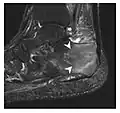

Figure 8: Proximal diaphyseal fatigue fracture of the tibia in a 20-year-old man with a history of regular jogging. (a) Lateral radiograph shows no obvious fracture lines but a subtle localized medial tibial cortex periosteal reaction (arrows). (b) Sagittal reformatted CT image acquired 1-month after the radiograph shows a linear hypoattenuation in the tibial cortex (arrowhead), as well as obvious periosteal thickening (arrows). (c) Sagittal T2-weighted fat-saturated image acquired the same day shows an area of hyperintensity spreading over the proximal tibia (arrows), which is consistent with the presence of proximal tibial fracture.[1]

Figure 9: Proximal metaphyseal fatigue fracture of the tibia in a 27-year-old recent male military recruit. (a) Anteroposterior radiograph is within normal limits. (b) Coronal T1-weighted MR image shows a marked linear hypoattenuation along the medial tibial metaphysis (arrow) surrounded by diffuse hypointensity in keeping with posttraumatic edema.[1]

Figure 10: Calcaneal fatigue fracture in a 30-year-old male runner. Radiographs were normal (not shown). (a) Sagittal T1-weighted and (b) short tau inversion recovery images show a linear hypointensity (arrows) of calcaneal tuberosity within diffuse bone marrow edema, which appears as an ill-defined area of hyperintensity on a fluid sensitive pulse sequence (arrowheads).[1]